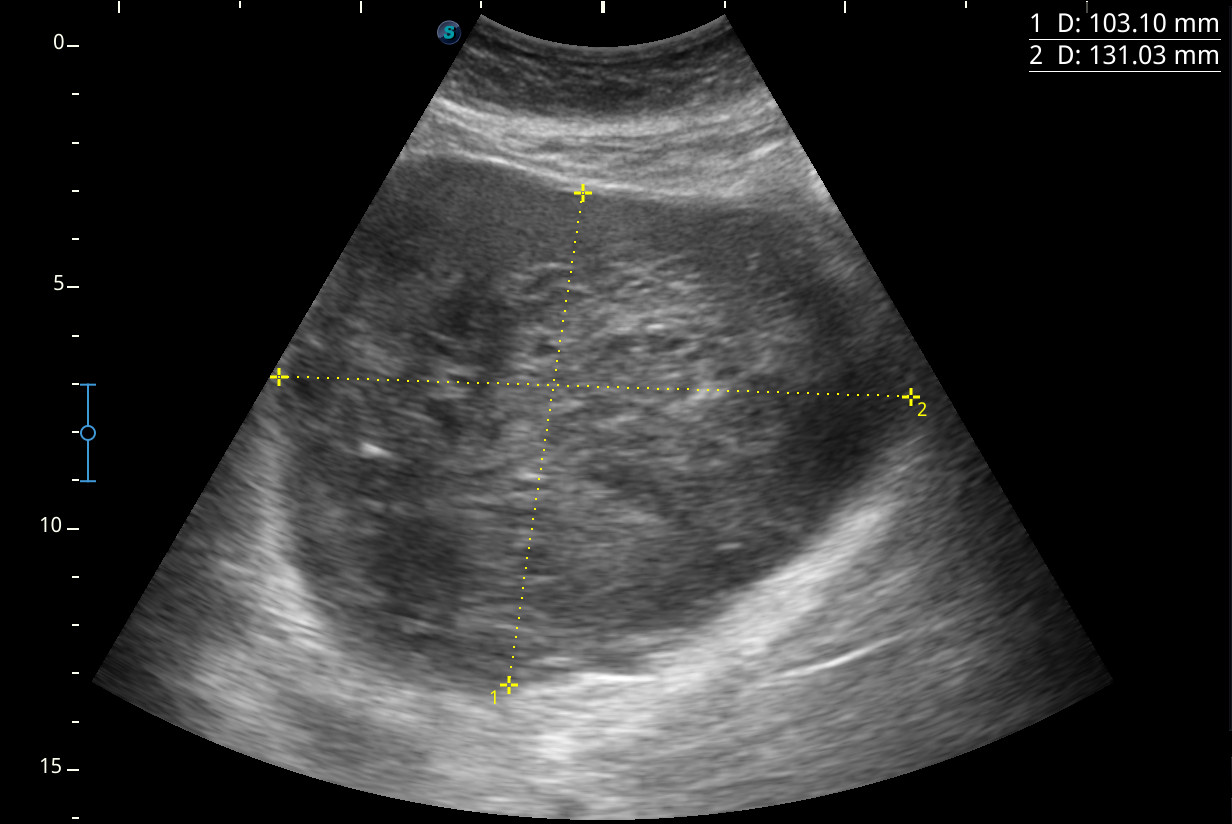

Hallazgos ecográficos

Se visualiza una masa heterogénea de unos 10 x 13 cm aproximadamente de diámetro con posibles focos necróticos y captación Doppler color, de dudosa organodependencia, que podría corresponder a un sarcoma retroperitoneal.